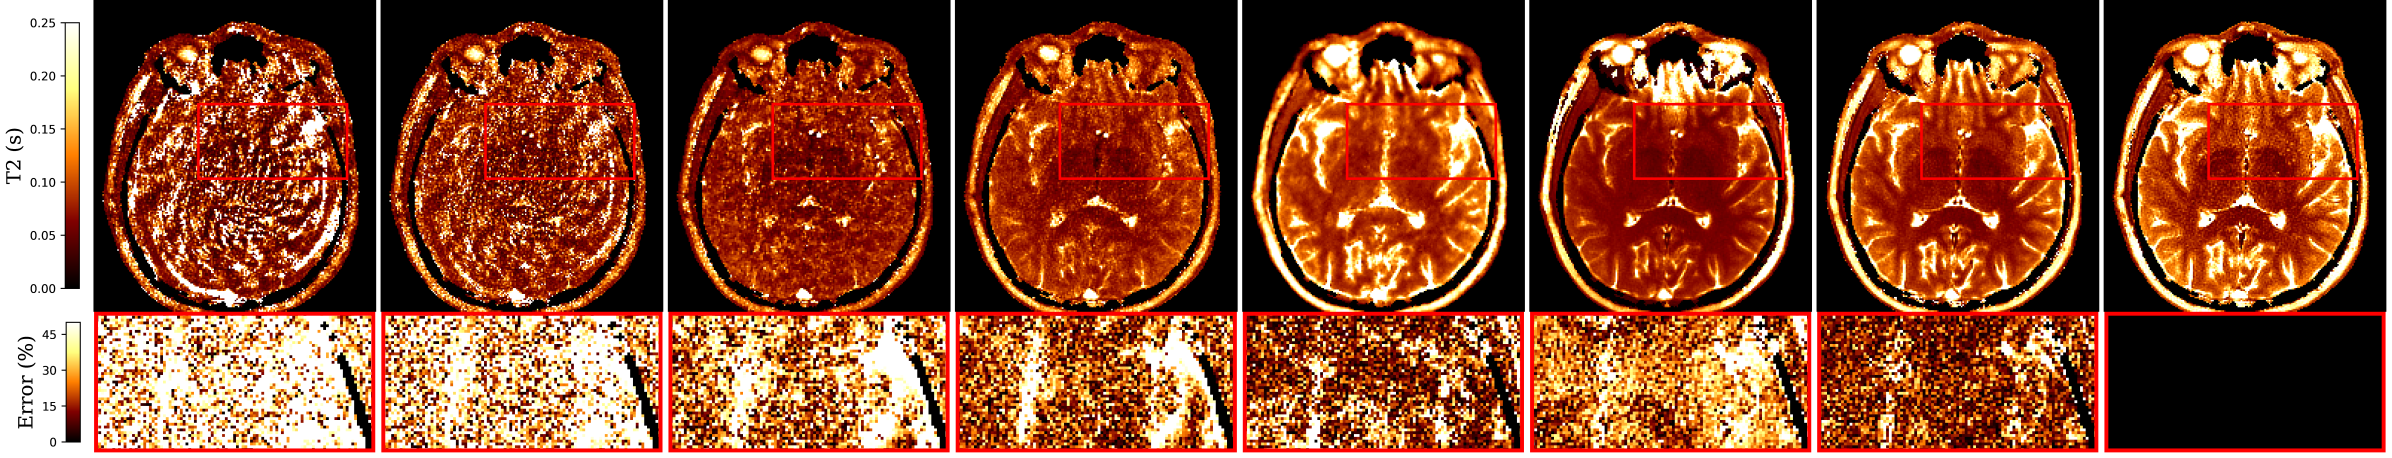

MRF-DiPh outperforms the tested baselines across all reconstruction metrics (Table 1), improving T1 MAPE by 2%, T2 MAPE by , and TSMI NRMSE by . Figure 1 compares the reconstructed T1 and T2 maps, showing MRF-DiPh with fewer errors and more defined anatomies. Table 1 shows that MRF-DiPh outperforms the purely data-driven MRF-IDDPM not only in quantitative mapping, but also in k-space fidelity by less errors, leveraging physics-informed guidance during reconstruction. Enforcing only k-space consistency along with DDM (ablated case C) improved performance over MRF-IDDPM, while adding Bloch consistency (MRF-DiPh base) further enhanced qmap reconstructions. A trade-off exists with k-space consistency–weak or absent image priors can lead to overfitting, introducing artifacts from noisy undersampled data (see LRTV, ADMM-MRF).

In our experiments, the unconditional model (MRF-DiPh D) improved upon SVDMRF, ADMM-MRF and LRTV methods. However, it underestimated T2 maps, particularly around grey matter and CSF areas (Fig. 1), falling short of conditional/supervised learning baselines. The embedded conditioning in our base model was able to resolve this challenging task. Therefore, exploring the application of unconditional MRF-DiPh in other acceleration schemes – such as further k-space subsampling, rather than truncating the sequence length – requires further investigation.